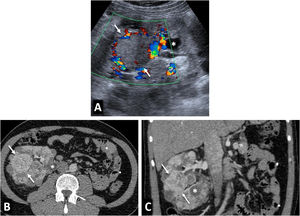

Von Hippel-Lindau syndrome. A 40-year-old male under follow-up for Von Hippel-Lindau syndrome with a genetic diagnosis and a previous left nephrectomy. In the follow-up with ultrasound and colour Doppler (A), a solid nodular lesion measuring 41 mm (arrows) is detected, confirmed by CT in the nephrographic phase (B and C) and susceptible to selective resection. Renal cysts are also visible (*).